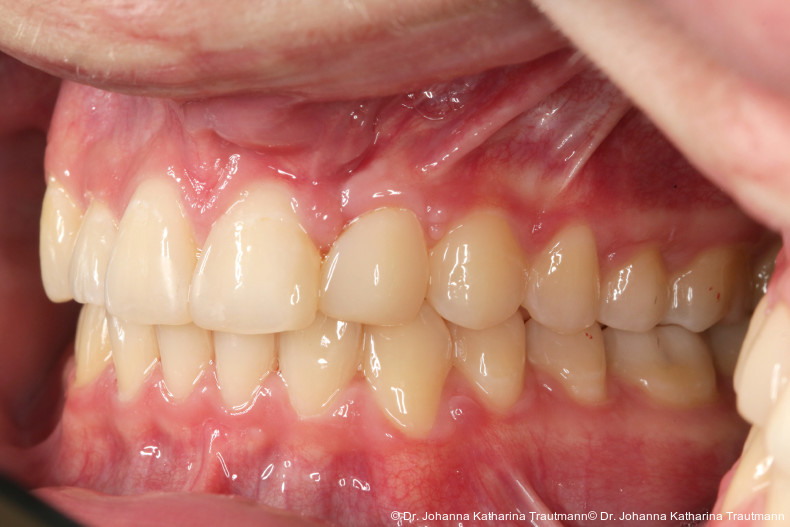

Längere Retentionszeiten ohne odontoplastischen Umbau können das Risiko eines Rezidivs des Zahnes 22 erhöhen. Dennoch ist häufig eine Abheilphase nach der Multibrackettherapie erforderlich, da sich gingivale Entzündungen oft erst nach ein bis drei Monaten vollständig zurückbilden.19–21 Um diesen Zeitraum zu überbrücken wurde an 22 die Kunststoffbasis der DVP (Doppel vorschubplatte) zur Retention sowohl mesial als auch distal extendiert. Schließlich wurden die Zähne 11, 21 und 22 kompositrestaurativ angeglichen, wodurch ein sehr gutes ästhetisches Ergebnis erzielt wer den konnte. Aufbauten mit Komposit bieten eine gute Möglichkeit, bei maximaler Schonung der Zahnhartsubstanz hypoplastische Zähne langfristig zu versorgen, und zeigten in ZehnJahresFollowups hohe Überlebensraten. Entscheidend ist hierbei eine ausgeglichene okklusale Lastverteilung, die mit hilfe einer physiologischen Frontzahnabstützung und gesicherten Okklusion durch die kieferorthopädische Vorbehandlung erreicht werden kann.22

Zur objektiven Quantifizierung des Behand lungsergebnisses wurde der Peer Assess ment Rating(PAR)Index erhoben.23 Im vorliegenden Fall konnte der PAR-Wert von 25 auf zwei reduziert werden, was einer Verbes serung von 92 Prozent entspricht und als hoch wertiges okklusales Ergebnis einzustufen ist.24 Zur Vorhersage der Langzeitstabilität bei Spalterkrankungen lässt sich dieser Fall in die Gruppe 1 des GOSLON Yardstick Index ein ordnen. Dieser sagt eine exzellente Langzeitstabilität vorher.25 Auch der Patient zeigte sich mit dem Ergebnis sehr zufrieden. Während der anderthalbjährigen Retentionsphase erfolgte zusätzlich eine ästhetische Nasenkorrektur zur Aufrichtung des linken Nasenflügels, wodurch neben der dentalen auch die extraorale Rehabilitation erfolgreich abgeschlossen werden konnte.